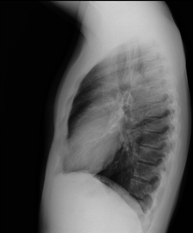

- Thoracic spine X-ray

This technique uses X-ray rendered imaging for examining the thoracic spine. Indicated for: trauma, pain, scoliosis.

This technique uses X-ray rendered imaging to examine the thoracic spine. Indicated for: trauma, back pain.